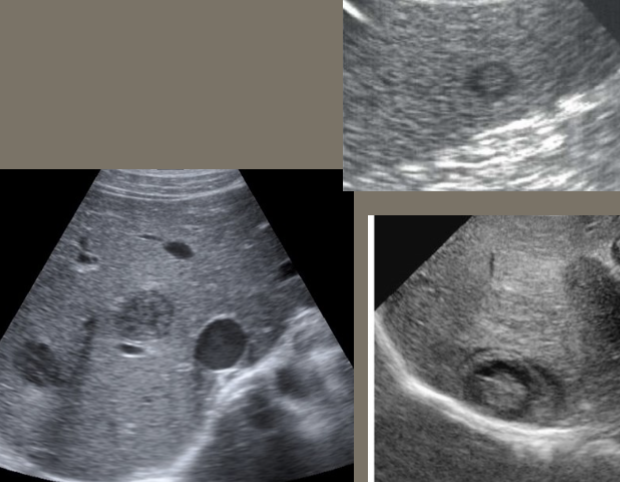

Simple Renal Cyst → common lesion of kidney, fluid-filled sac (benign, Bozniak 1)

clinical hx: incidence increases with age (50+), uncommon in children

s/sx: asymptomatic

2D US: anechoic, well-defined smooth, thin wall, round or ovoid, posterior enhancement

color doppler: avascular

DDX: complex cyst

Complex Renal Cyst → any cyst that is not a simple cyst

clinical hx: post-surgery, trauma

s/sx: flank pain, fever, hematuria, WBC increase, can be asymptomatic

2D US: well-defined cystic structure, internal echoes or anechoic, septations, focal hypoechoic inner mural extension, can be hemorrhagic

color doppler: if solid can have vascularity

DDX: malignant tumor, RCC